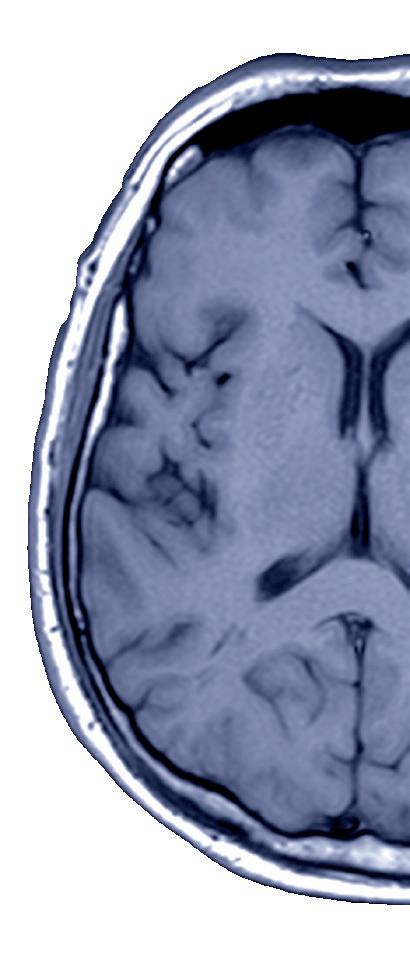

Every hour saved between stroke onset and thrombectomy could equate to 25% greater odds of functional independence

A systematic review and meta-analysis of five studies and more than 11,000 patient records has indicated that each hour saved between acute ischaemic stroke symptom onset and initiating a mechanical thrombectomy procedure is associated with a 22–25% increase in the odds of achieving functional independence.

The review and analysis in question—dubbed ‘SWIFTEVT’—has been published in the Journal of Stroke and Cerebrovascular Diseases by Brittney Legere (University of Guelph, Guelph, Canada) and colleagues.

“While other systematic reviews have similarly analysed previous onset to EVT [endovascular therapy] time effects on patients, SWIFT-EVT provides a more recent and thorough analysis evaluating good and excellent functional independence,” Legere et al note. “Quantifying this substantial time-dependent benefit, relevant during the entire first six hours post-acute ischaemic stroke onset, may be useful to inform patient-specific and systems planning decisions.”

The researchers initially state that data through 2014 from the HERMES meta-analysis demonstrated that—particularly over the first six hours post-acute ischaemic stroke—the rapid administration of thrombectomy treatment “markedly improves outcomes”. However, while subsequent analyses and studies have further elucidated how ‘time to thrombectomy’ affects outcomes, “no recent systematic reviews have quantified patient outcomes based on time intervals, and the time-saving benefit of EVT”. Against this backdrop, SWIFT-EVT set out to calculate precise, patient-centred outcome benefits for incremental pre-

thrombectomy time savings within six hours of stroke onset—a “broadly accepted” and guideline-based window for prioritising EVT timings in large vessel occlusion (LVO) stroke patients.

The investigators’ aim was to provide “an updated metric summarising latest estimates for modified Rankin scale [mRS] improvements accrued by streamlining time to EVT”.

included five studies; four large, national/international registries—the 2017 STRATIS, 2018 MR CLEAN-R, 2018 Trevo Retriever and 2019 Get With The Guidelines (GWTG)-Stroke registries—as well as the 2020 Triveneto registry from a single Italian region. In combination, these studies comprised data from 11,343 patients. The researchers’ primary endpoint was the rate of functional independence (mRS 0–2) at 90 days, while rates of 90-day ‘excellent function’ (mRS 0–1) and mortality, and level of occlusion, were among key secondary endpoints.

Their results ultimately revealed an increased chance of a good functional outcome, defined as mRS 0–2, with each hour of pre-EVT time savings—a trend that

was present within an earlier time window of 0–270 minutes (odds ratio [OR], 1.25) and a later timeframe of 271–360 minutes (OR, 1.22). Legere et al report that, for each hour saved within the earlier timeframe, the odds of achieving functional independence improved by 25%, with these odds only diminishing slightly to 22% in the later window. In addition, within those studies assessing excellent function, the authors go on to note that comparable trends were observed at timeframes of both 0–270 minutes (OR, 1.34) and 271–360 minutes (OR, 1.20), as the odds of achieving mRS 0–1 were found to increase by 34% and 20%, respectively, with each hour saved. Legere et al also detail that—across their primary and secondary endpoint results on mRS 0–2 and mRS 0–1—“Cochrane’s Q, a reassuring Galbraith graph, and fixed-effects modelling, provided support for a finding that heterogeneity was not present to a degree precluding generation of a pooled effect estimate”.

In addition, the authors state that their analysis was ultimately unable to demonstrate an effect of time savings on mortality, with this being noted for both the early (p=0.68) and late (p=0.71) timeframes. However, they do relay that three included studies reported on the level of occlusion in relation to time savings, with sensitivity analyses to determine any alteration of their overarching findings when including only these studies

revealing that heterogeneity remained acceptable (27.45 %) and each hour saved was estimated to be associated with increased survival (OR, 1.35).

“Quantifying the benefit of faster time to EVT is of critical importance for design and improvement of stroke systems of care,” Legere et al write, discussing their results in greater detail. “Many patients who experience stroke are not near EVT-capable hospitals— over a third of the US population has EMS [emergency medical services] transport time of greater than one hour to a comprehensive or EVT-capable stroke centre.

“Our systematic review and meta-analysis estimated that—within the initial six hours—for every 20 cases of 60-minute reduction in time from LVO acute ischaemic stroke symptom onset to EVT start time, there was one additional case of functional independence.

“Importantly, our findings were based on calculations using a denominator of all EVT cases, so SWIFT-EVT estimations can be broadly useful in application to triage and transfer decisions that are necessarily made without full knowledge (or foreknowledge) of variables such as advanced imaging results or reperfusion success. While not definitive, SWIFT-EVT’s calculations may be useful for systemwide organisation and planning of medical care, as well for those making individual patient triage decisions.”